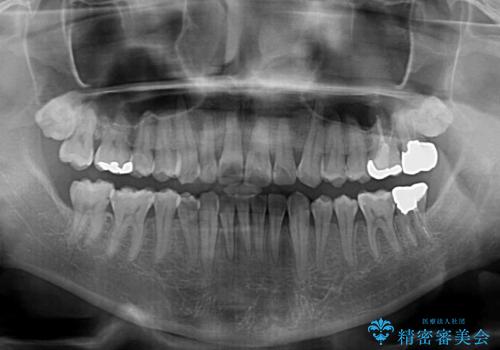

- 上下前歯の叢生を気にして来院された患者様です。

奥歯はクロスバイトとなっているので上顎は側方拡大を行いつつ、上下全体の叢生をインビザラインにより改善することとしました。

治療途中でクリーニングやホワイトニングを行い、歯列が整うと同時に明るい口元となりました。